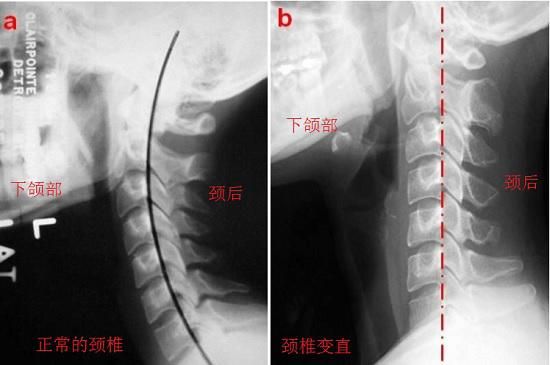

2、恢复颈椎关节正常的排列顺序,在一定程度上具有颈椎关节畸形校正功能。